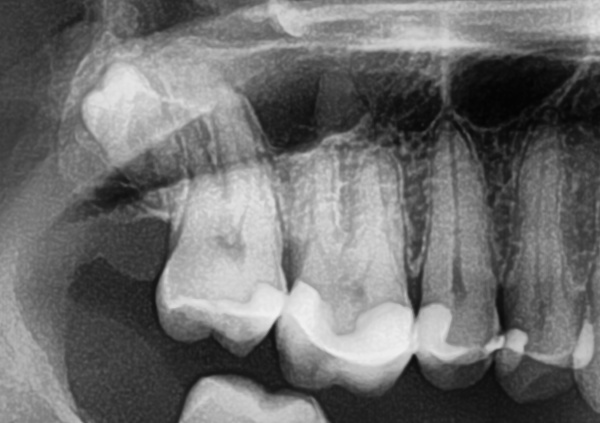

34-jähriger Patient (18.12.2023 / 2753)

Der Weisheitszahn hat ein besonderes Wurzelwachstum wegen dem canalis mandibularis (rot). Er scheint die Wurzeln zu verbiegen und die Wurzelspitzen zu verdicken.